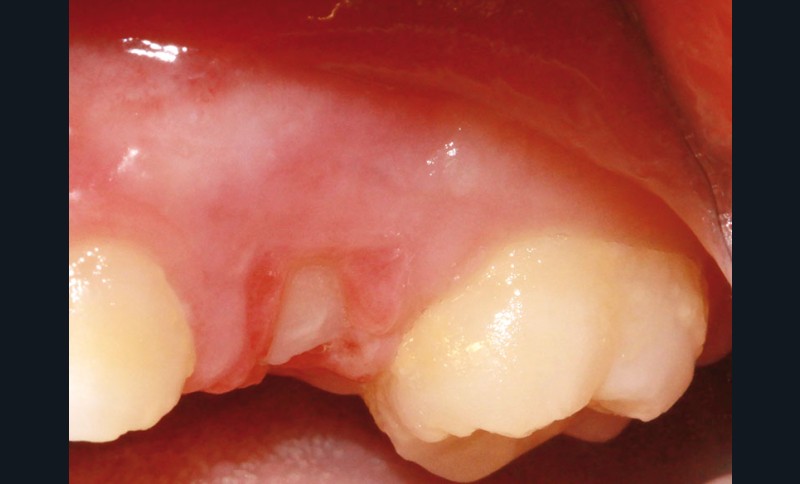

L’examen clinique révèle la présence d’une ulcération végétante, d’environ 1 cm de diamètre, localisée sur les gencives marginale, papillaire et attachée en vestibulaire de 55 et 16, associée à une récession parodontale pour 55. L’ulcération est bien délimitée, indolore et non hémorragique spontanément. Les dents présentent une mobilité physiologique et il n’existe pas d’adénopathie.